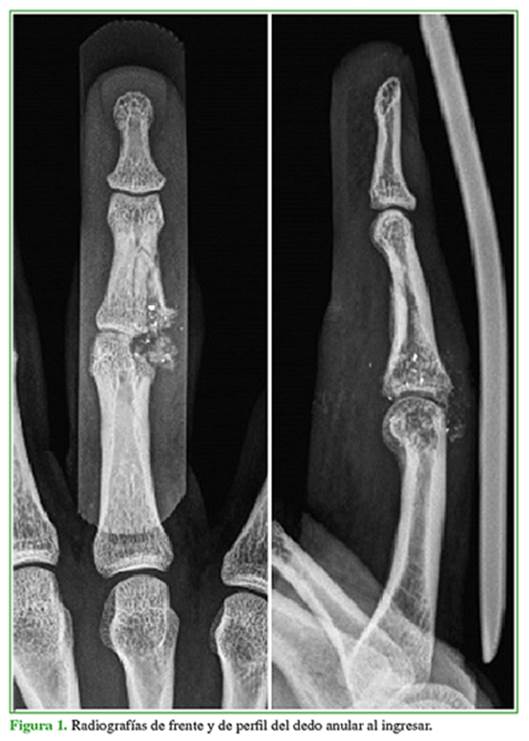

Hombre de 27 años que sufrió una fractura expuesta por proyectil de arma de fuego con orificio de entrada y salida, en la articulación interfalángica proximal del dedo anular de la mano derecha. En las radiografías, se observó un compromiso del 40% de la superficie articular en su sector cubital (con defecto en la región distal de la primera falange y proximal de la segunda falange); además, la fractura se extendía a la diáfisis de la segunda falange (Figura 1).